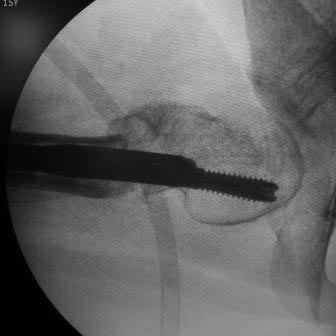

Уважаемые коллеги. Больная оперирована 06.03.15г клинок был сломан,

и пока его с трудом  удалили  от неполноценного вертела почти ничего не

осталось,сломанный шуруп тоже удален, шейка совсем короткая, , ШДУ

около 95гр, из-за сильного остеопороза при сверление в положении чуть

вальгуса наружная стенка крошится , и еще что интересно при первой

операции головка бедра оказалось фиксирован в положении ретроверсии

примерно 10-15 гр.. и с трудом удалось выпрямить головку и шейку до 0

гр. , укорочение было чуть больше 1см , п/о -2см, пока фиксация гипсовый

сапожок с деротатором. Дальше как быть? Может временно фиксировать